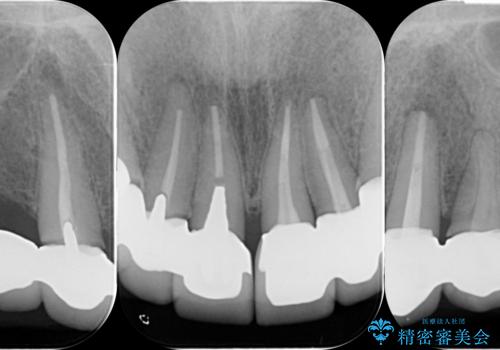

前医により、前歯は歯ぐきの奥深くまで形成されこのままの状態でセラミックをやりかえたとしても歯ぐきの腫れの改善は難しい状況です。

歯周外科を行い歯と歯槽骨・歯肉の関係を是正することで歯ぐきの状態を改善し、将来に亘り安定した歯周環境の維持を期待できるセラミック治療を実践します。